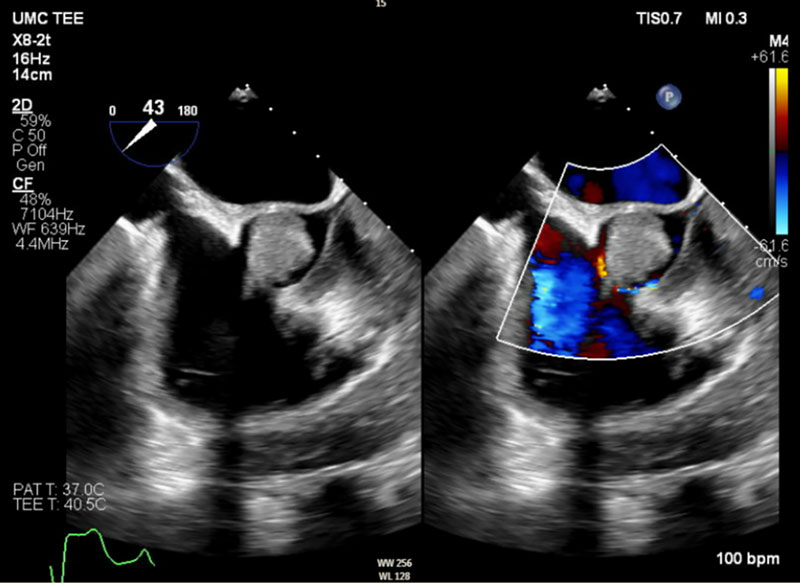

A 54-year-old male with a history of systemic lupus erythematous (SLE) and antiphospholipid syndrome (APS) on apixaban presented to the ED with symptoms and preliminary workup consistent with an ongoing non-ST-elevation myocardial infarction (NSTEMI). Prior to planned left heart catheterization (LHC), transthoracic echocardiogram identified a large thrombus/vegetation on his aortic valve. In light of this finding, the LHC was aborted to prevent catheter embolization of the lesion (engagement of the coronary arteries requires close catheter articulation with the aortic valve leaflets), and transesophageal echocardiogram (TEE) was subsequently performed to better visualize/characterize the mass. By TEE imaging, it measured up to 2.7 cm, nearly the diameter of the left ventricular outflow tract (LVOT) itself (Figure 1). The turbulent forward flow caused by functional LVOT stenosis (due to partial obstruction resulting from the large size of the mass relative to the outflow tract) was also appreciated (Figure 2), with mild to moderate aortic regurgitation also seen. After negative blood cultures suggested sterility of the lesion, this patient underwent surgical resection of the mass and replacement of his aortic valve with a tissue valve. Lack of growth on bacterial and fungal tissue culture from samples of the valvular vegetation obtained during surgery, in addition to his clinical history, provided support for the diagnosis of Libman-Sacks endocarditis. He had an uneventful postoperative inpatient recovery course before eventual discharge to home on warfarin.

Figure 2

Figure 2 Long-axis TEE view with addition of color Doppler allows appreciation of the turbulent flow around the AV vegetation.

TEE, transesophageal echocardiogram. AV, aortic valve. LVOT, left ventricular outflow tract.